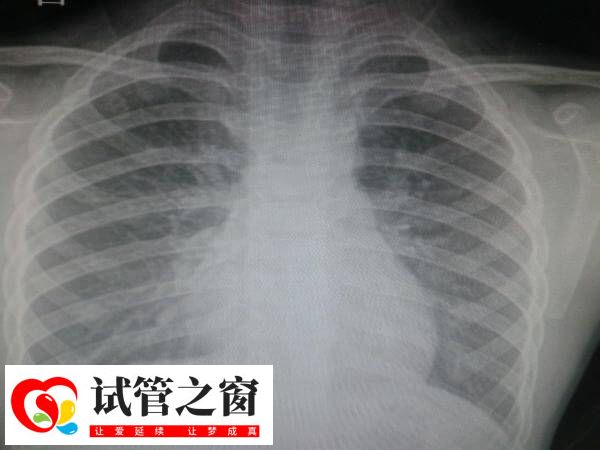

在进行试管婴儿治疗前,拍摄胸片是一项常规的身体检查项目,一般试管患者做该项检查,通常是为了排除肺部疾病,如肺结核、肺炎、肺部肿瘤等,以确保身体条件适合进行试管婴儿治疗。如果患者有异常疾病的情况下,需要及时前往医院就诊,以免影响接下来试管治疗的成功率。

做试管的目的是获得妊娠并成功生产,而女性妊娠前一定要确保身体的健康,这时会进行拍摄胸片检查。一般准备做试管的女性朋友通过拍摄胸片,如果发现有心脏病、肺结核、肺部结节疑似恶性病变等情况,就需要先处理原发疾病,治愈后再开始试管治疗,以确保以良好的身体状况迎接宝宝的到来。

所以可见,胸片还能评估心脏大小和形态,排除心脏疾病对妊娠的潜在影响,并查看胸廓情况,观察是否存在畸形或异常。这些检查为后续的治疗和手术提供参考依据,确保整个试管婴儿过程的安全性。